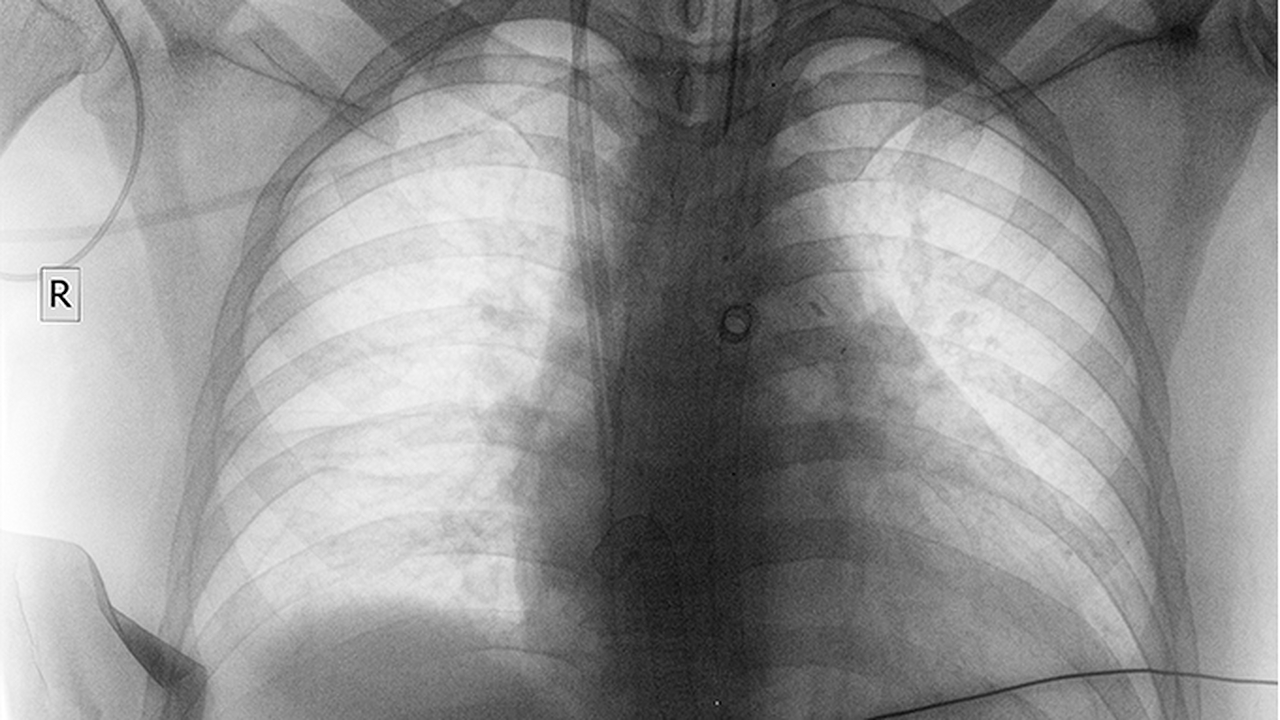

肺癌是一种常见的恶性肿瘤,其发病原因复杂,包括吸烟、空气污染、职业暴露等多种因素。早期诊断和规范治疗对提高患者生存率至关重要。